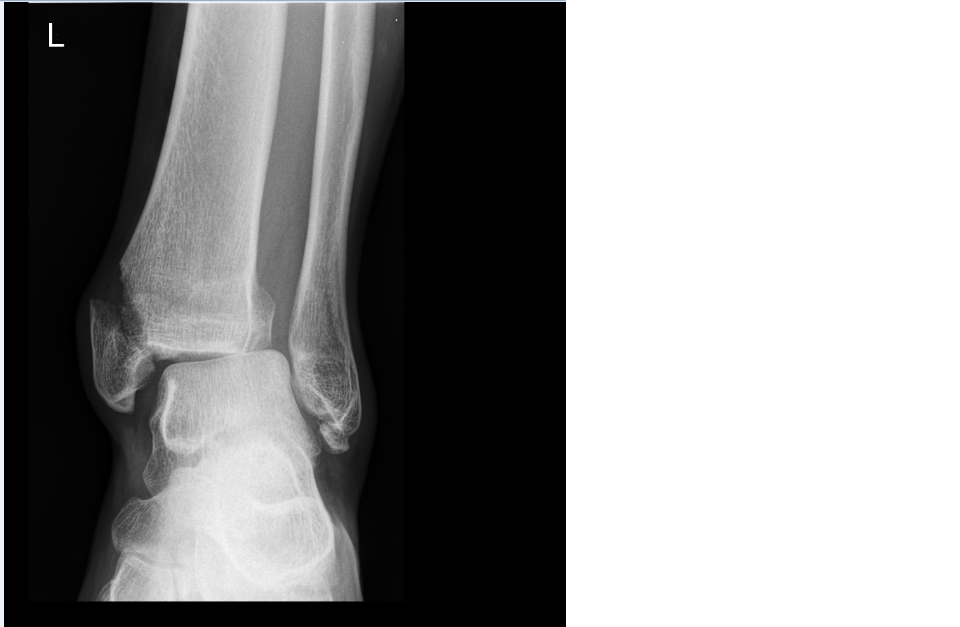

wie schauts jetzt eigentlich aus? hat das innengelenk was abgekriegt oder hast dir den fuss sauber oberhalb des knöchels abgebrochen? sag bescheid wenn du in die reha kommst, mein physio hat ein paar tips für dich.unkonventionelles hüpfen von couch zum klo...